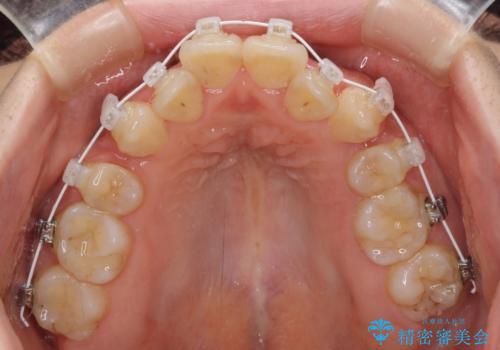

- 矯正装置

- 審美装置

- 前歯の著しいデコボコを気にして来院された患者様です。

上顎の左右側切歯(前から2番目)が裏側に隠れいてる状態で、咬み合わせや清掃性に大きな問題が認められました。

叢生が著しいため、左下以外の第一小臼歯3本を抜去し、目立たないワイヤー装置にて矯正治療を行うこととしました。

これほど顕著に裏側に隠れいてる歯ですと、仕上がったときに両隣の歯と軸に差が認められることが多いのですが、殆ど違和感のない歯並びを達成することができました。